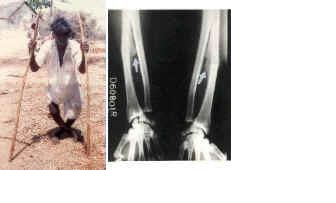

10. 5 Feb, 2013 Research Article

Medical Geology: A Globally Emerging Discipline

Authors: V. Sunitha, M. Ramakrishna Reddy

DOI: | Pages: 57-64

Article Image